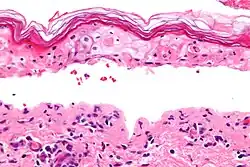

| Método de diagnóstico | <10% da pele envolvida, biópsia da pele[2] |

Para o diagnóstico de SSJ é necessário que a área de pele afetada seja inferior a 10% da superfície do corpo.[2] Quando mais de 30% da pele é afetada considera-se NET, e entre 10 e 30% considera-se forma intermédia.[3] Acredita-se que as reações SJS/TEN seguem um mecanismo de hipersensibilidade do tipo IV (não imediata).[5] A SSJ/NET faz parte de um grupo de doenças denominado reações adversas cutâneas graves (SCAR), do qual também fazem parte a síndrome induzida por fármacos com eosinofilia e sintomas sistémicos (síndrome DRESS) e a pustulose exantemática generalizada aguda (PEGA).[6] O eritema multiforme (EM) é geralmente considerado uma doença distinta.[7]